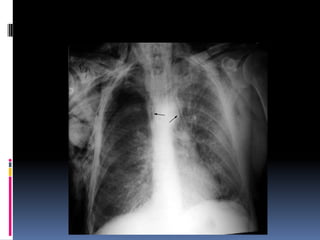

Heart

   Size

   Shape

   Silhouette-margins should be sharp

   Diameter (>1/2 thoracic diameter is

enlarged heart)

 AP views make heart appear larger than it

actually is.